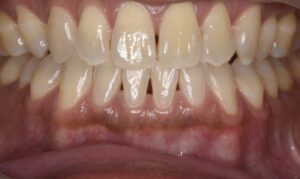

審美歯科